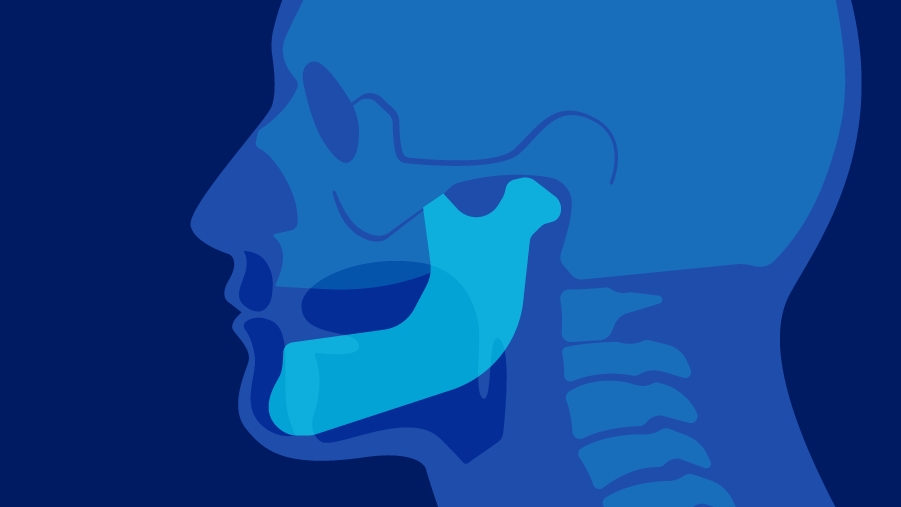

- The base of the tongue, swallowing mechanism

For the base of the tongue, major considerations include restoring the swallowing mechanism, preserving the tongue’s mobility, and resuspending the larynx to avoid aspiration. As flaps in this area must replace some of the volume of the resected defect, fasciocutaneous flaps are best.